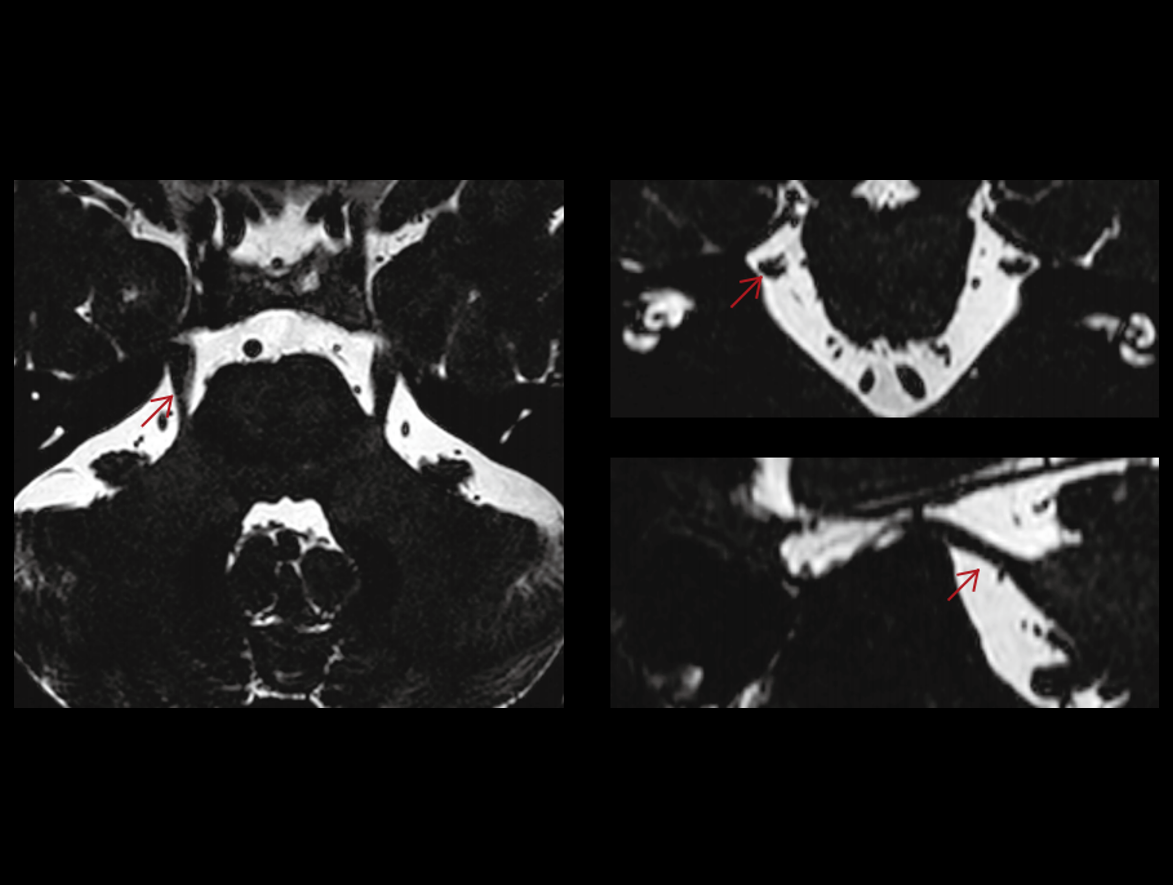

Potężny magnes 3,0 T ma krótką konstrukcję (170 cm), aby zapewnić wysoką jednorodność pola magnetycznego. Daje to solidne podstawy szybkiego obrazowania i doskonałego nasycenia tłuszczu w dużym polu widzenia, a także znakomitego obrazowania poza centrum.